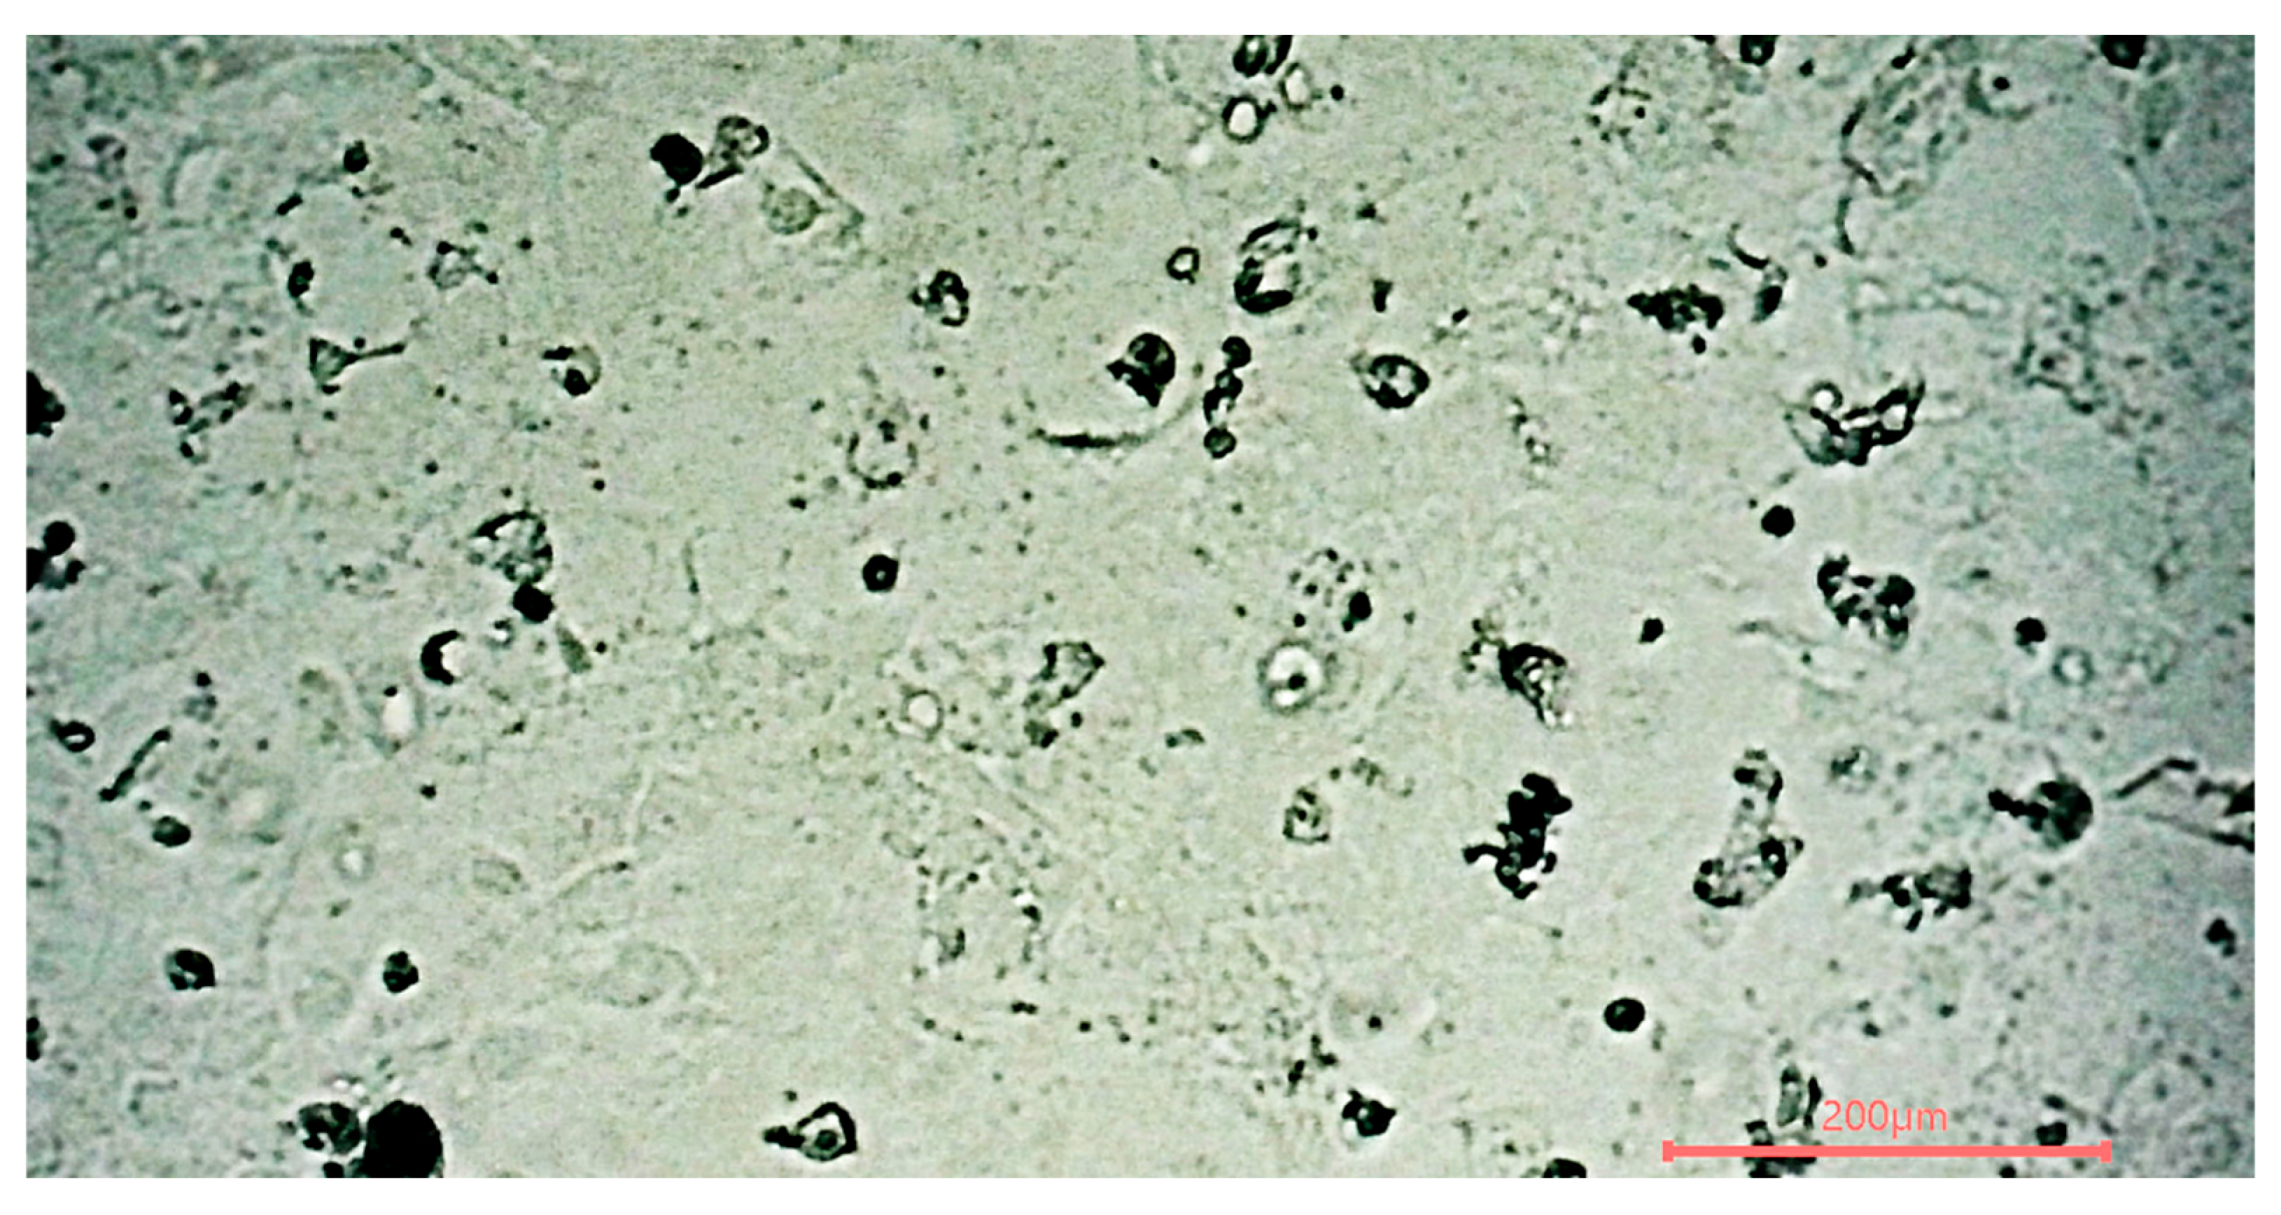

Figure 5.

Photo of the human colon cells cultivated post-sterilization under the microscope.

Residual toxicity for cell culture was only briefly qualitatively examined with S. cerevisiae, and epithelial cells isolated from human colon tissue with colorectal adenocarcinoma (CACO2 HTC-37) were expanded (Figure 5). Quick examination by eye and double time until cell confluence did not show any difference compared to culture in the regular non-ClO2-sterilized incubator. Also, in the literature, ClO2 toxicity was studied in vivo in rats [27]. Still, those data were insufficient to investigate whether the residual toxicity is acceptable for human cell-culture-based tests. Therefore, a quantitative assessment with robust immortalized human cell culture and fragile human cell culture should be performed to confirm that the residual toxicity does not impact human cell-culture-based tests.